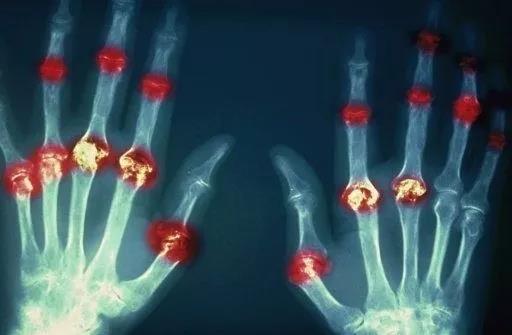

? 類風(fēng)濕關(guān)節(jié)炎

類風(fēng)濕關(guān)節(jié)炎是一種高度致殘的自身免疫性疾病,發(fā)病十年的患者中至少有50%的人失去勞動(dòng)能力。

類風(fēng)濕關(guān)節(jié)炎©Health Same of Flickr

1977年,Baldwin在用骨髓干細(xì)胞移植治療再生障礙性貧血的過程中,意外發(fā)現(xiàn)患者的類風(fēng)濕關(guān)節(jié)炎得到緩解。

2004年,歐洲骨髓移植和抗風(fēng)濕病聯(lián)盟對(duì)60例類風(fēng)濕病關(guān)節(jié)炎移植患者進(jìn)行回顧性分析,這些患者的關(guān)節(jié)破壞都達(dá)到不可修復(fù)程度,生活不能自理,通過干細(xì)胞移植治療后,67%的患者得到明顯緩解。

我國國內(nèi)多家醫(yī)院已開展了干細(xì)胞治療類風(fēng)濕性關(guān)節(jié)炎的臨床研究。首例自體干細(xì)胞移植治療類風(fēng)濕關(guān)節(jié)炎在北京協(xié)和醫(yī)院完成。經(jīng)過5個(gè)月隨訪,這些經(jīng)常規(guī)藥物治療失敗且病情發(fā)展迅速的患者,在接受干細(xì)胞移植治療后,癥狀均獲得改善,關(guān)節(jié)腫脹消失,各項(xiàng)檢查指標(biāo)恢復(fù)正常。

解放軍323醫(yī)院2011年的一項(xiàng)臨床研究中,27位患者(對(duì)照組)只使用藥物治療;另外153位患者(細(xì)胞治療組)在藥物治療的基礎(chǔ)上進(jìn)行臍帶間充質(zhì)干細(xì)胞輸注。結(jié)果顯示,治療組DAS28、HAQ 評(píng)分、ACR20較對(duì)照組下降明顯(分值越低,療效越好),Th1/Th2趨于平衡、Treg升高與臨床實(shí)驗(yàn)指標(biāo)及癥狀的緩解直接相關(guān)。